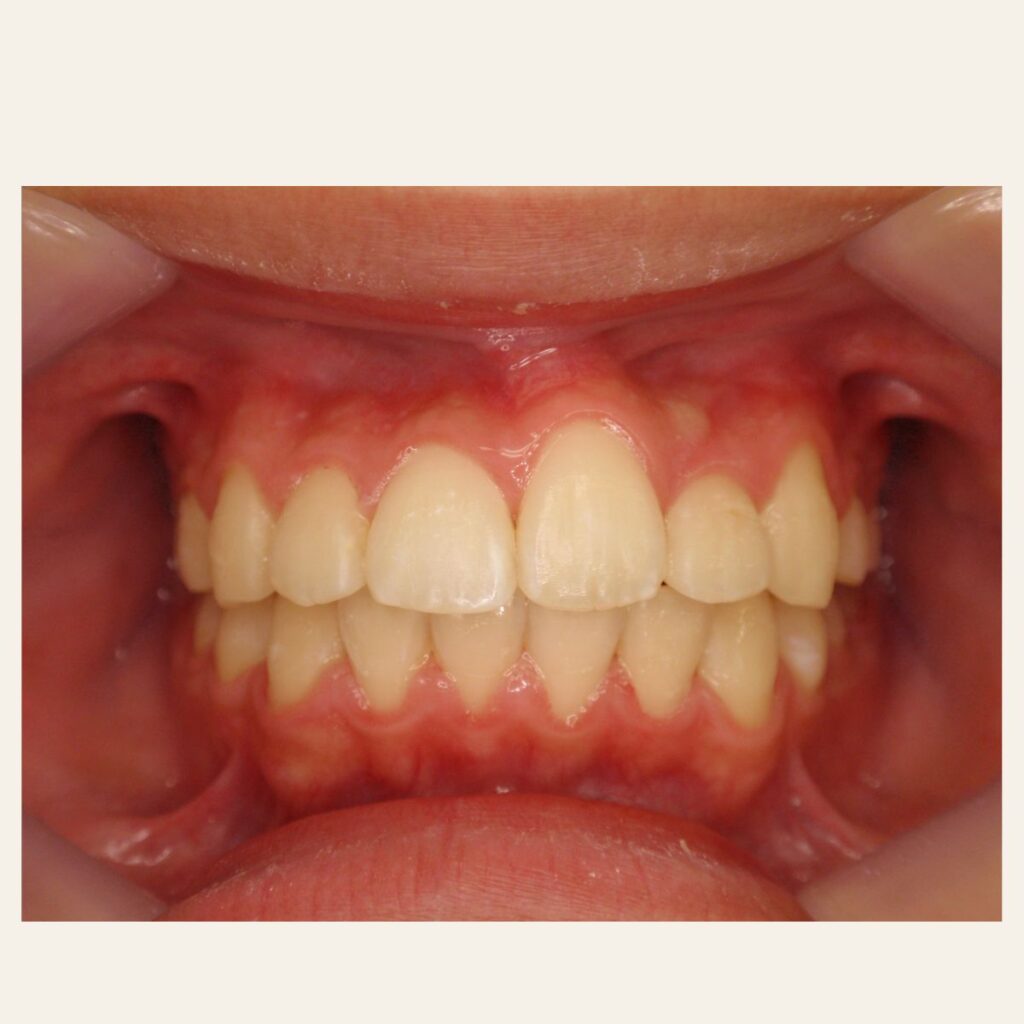

叢生の症例1(表側矯正)

治療前後(BEFORE/AFTER)

| 年齢 | 10代男性 |

| 主訴 | 前歯のガタガタ |

| 診断 | 叢生 |

| 治療方法 | 上下・表側ワイヤー矯正(今回抜歯はしていません) |

| 治療期間 | 11か月 |

| 費用 | 1,050,500円(税込) |

| リスク・副作用 | 痛み/歯根吸収/歯肉退縮/後戻り など |

本症例では歯が重なっている叢生と、前から見ると曲がっている状態でした。

歯列のスペースを確保しながら歯並びを整えるため、

表側矯正を用いて治療を行いました。

治療後は歯並びとかみ合わせが改善し、

見た目だけでなく歯磨きもしやすい状態になりました。

※虫歯の治療は矯正治療後に仕上げています。

※正中を合わせるには抜歯等が必要になる場合があります。